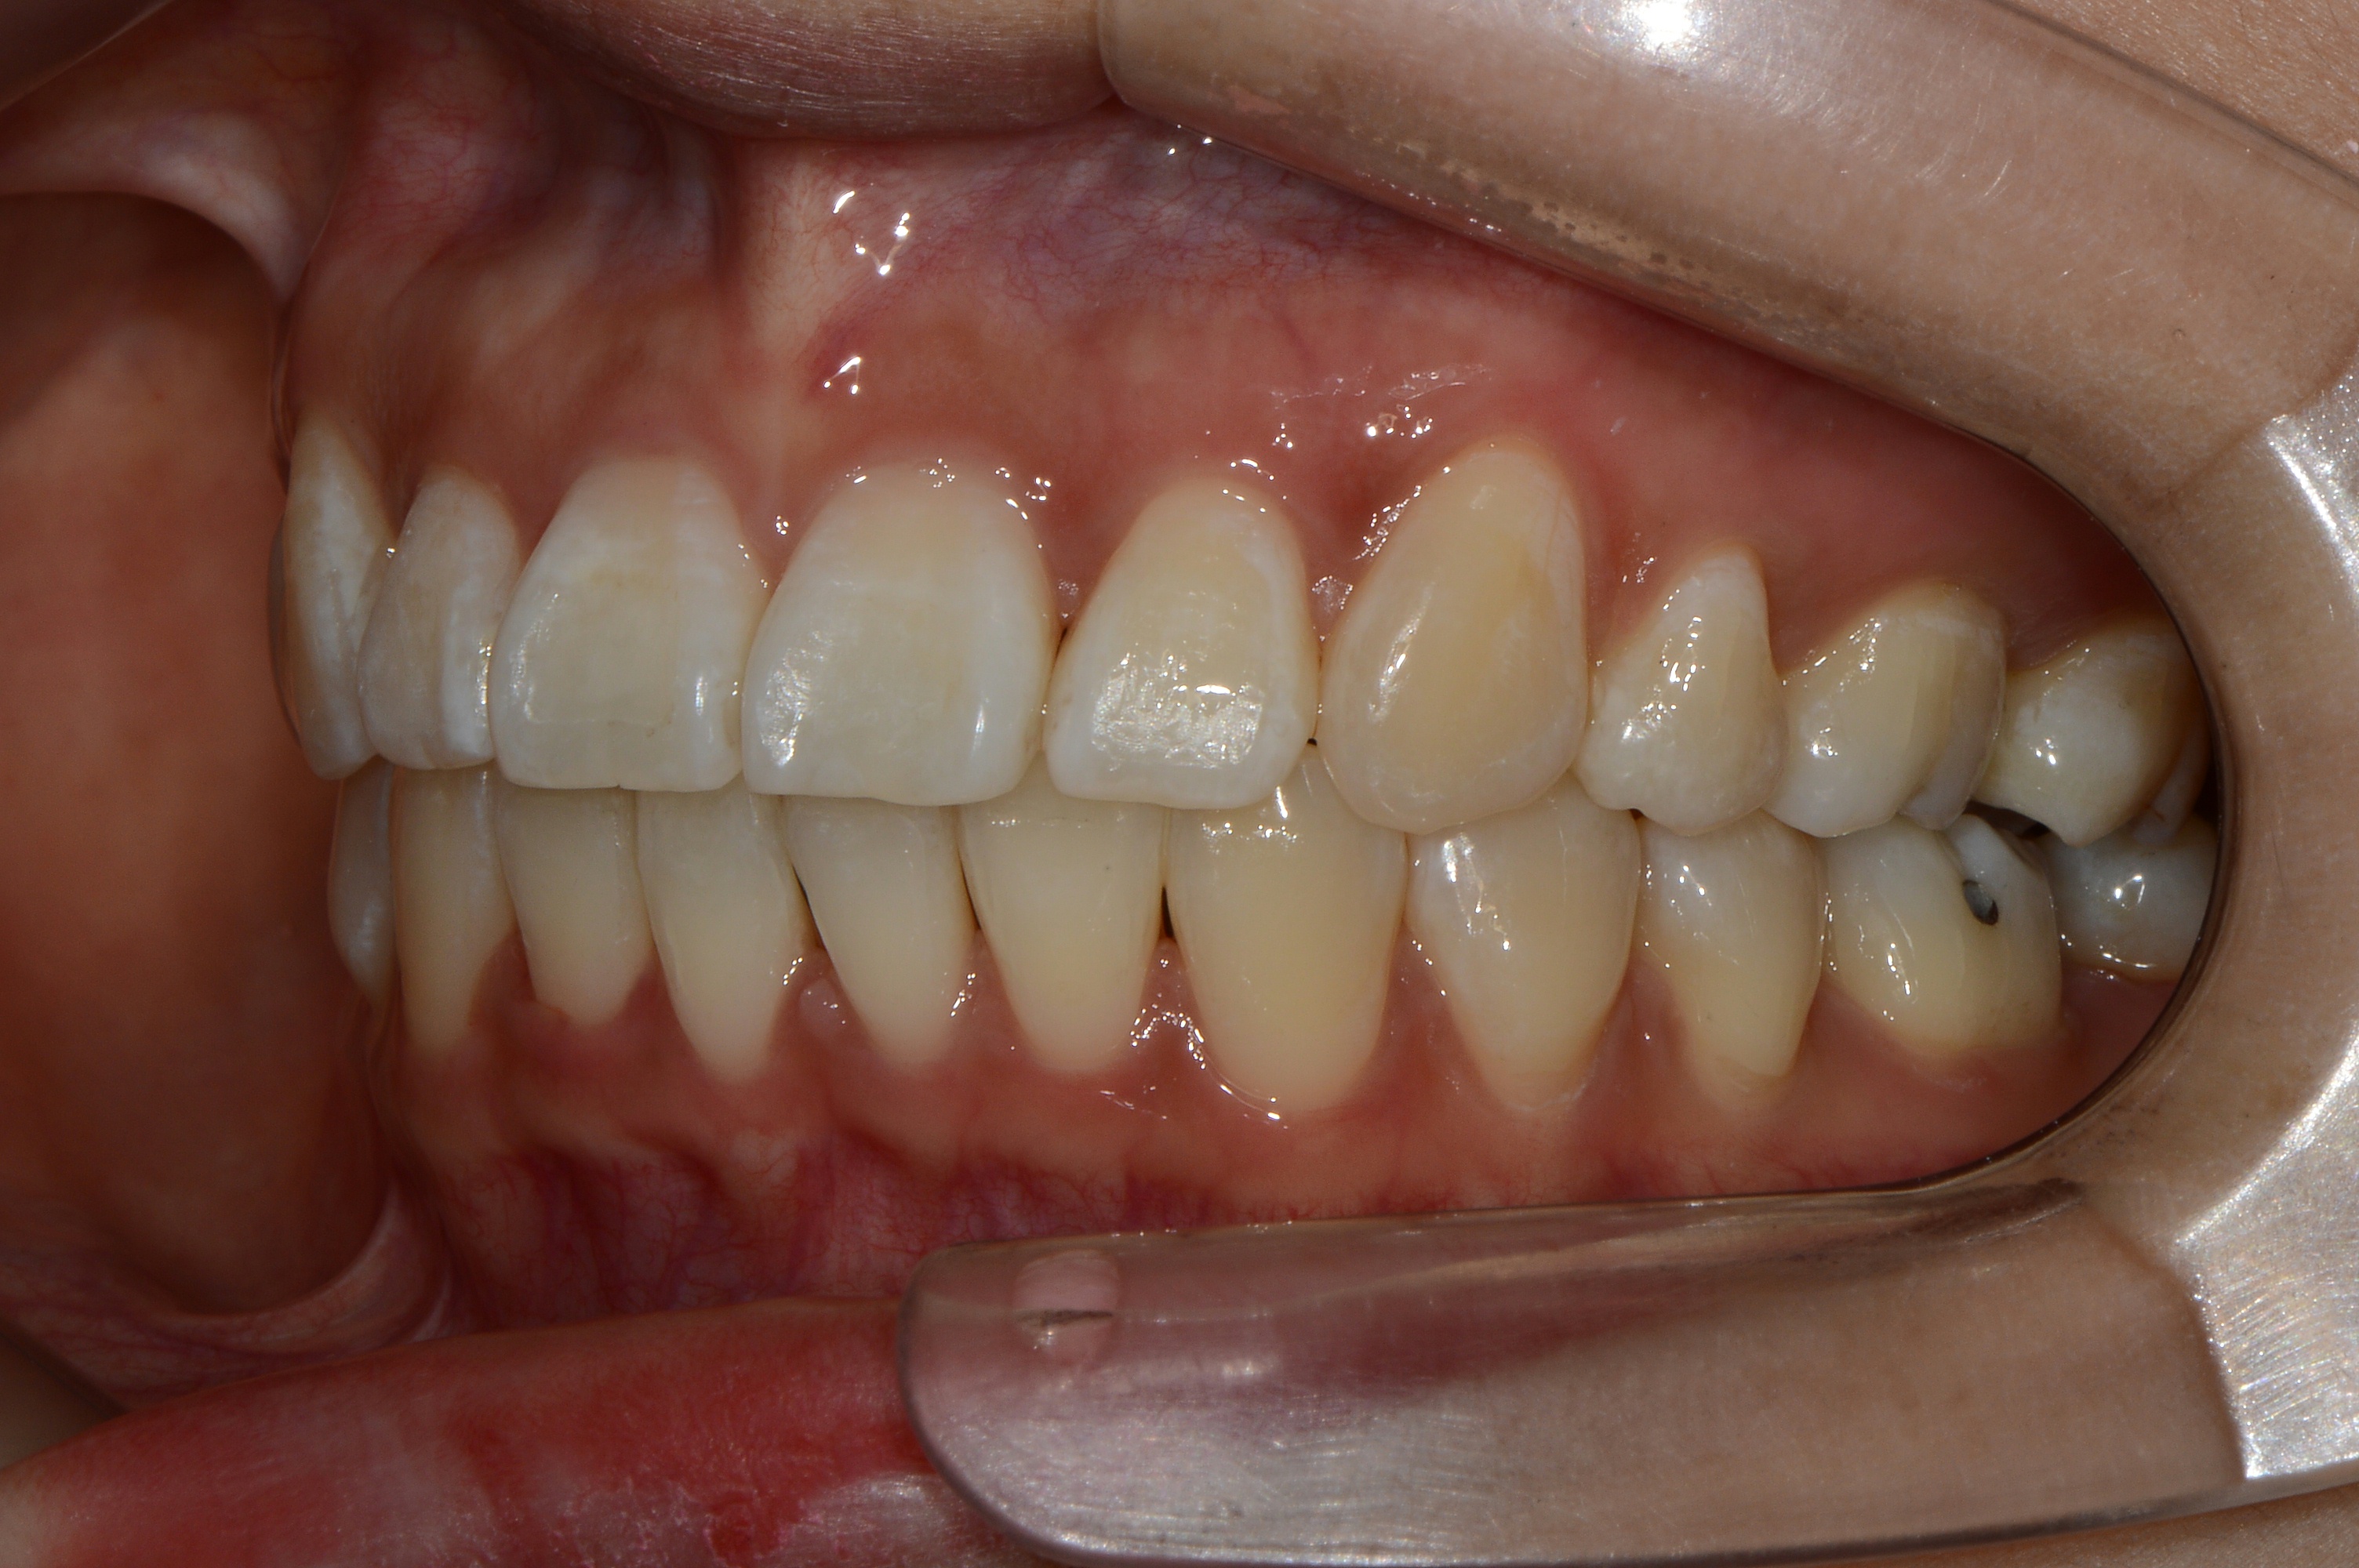

치료 후 사진입니다.